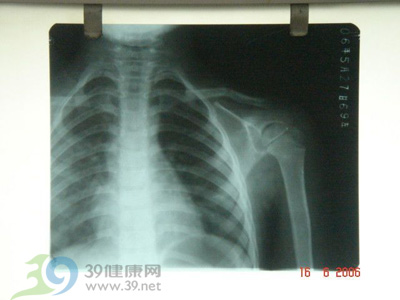

锁骨骨折

愈合期这一时期是指骨折经骨科处理后,到愈合前(拆除固定物前)的时期。此时活动较少,首先要保持科学的姿势,要求睡眠时在木板床上仰卧,两肩之间垫高,保持中间高、两肩低的“肩外展后伸位”。此外,要多做深呼吸,多活动躯干和下肢,并勤做握拳、伸指、分开手指、腕部屈伸、肘部屈伸等主动练习,幅度尽量大,逐步增加用力程度。

到了第二周,就可以增加捏小球,对抗阻力屈伸腕部等运动。到第三周,还可以增加仰卧位,头与双肘做支撑的挺胸练习。

恢复期外固定物去除后即进入此期。拆除固定物后的头两天,可将患肢用颈腕悬吊带挂在胸前,除继续上述练习外,还可增加站立位向患肢侧屈,做肩部的前后摆动,努力增加摆动幅度。第三至第四天,开始做肩关节各方向的主动运动。